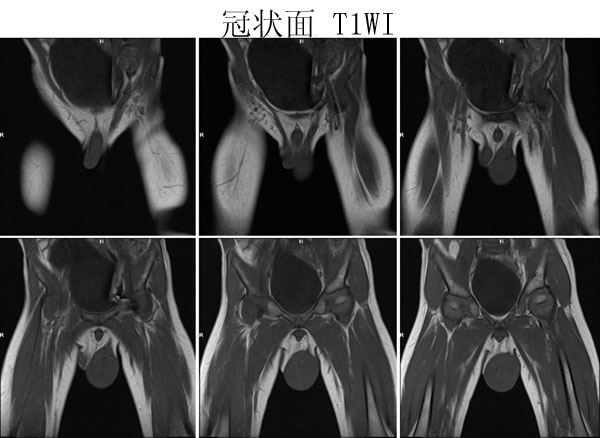

(广东同江医院的病例)男,2岁。左侧睾丸肿大3月,开始发现时红枣大,逐渐增大,现鸡蛋大小,表面光滑,无压痛,质地中等。

病理诊断 :(左侧)

睾丸胚胎性横纹肌肉瘤

,瘤组织局部浸润附睾组织,精索残端组织内未见瘤组织浸润。